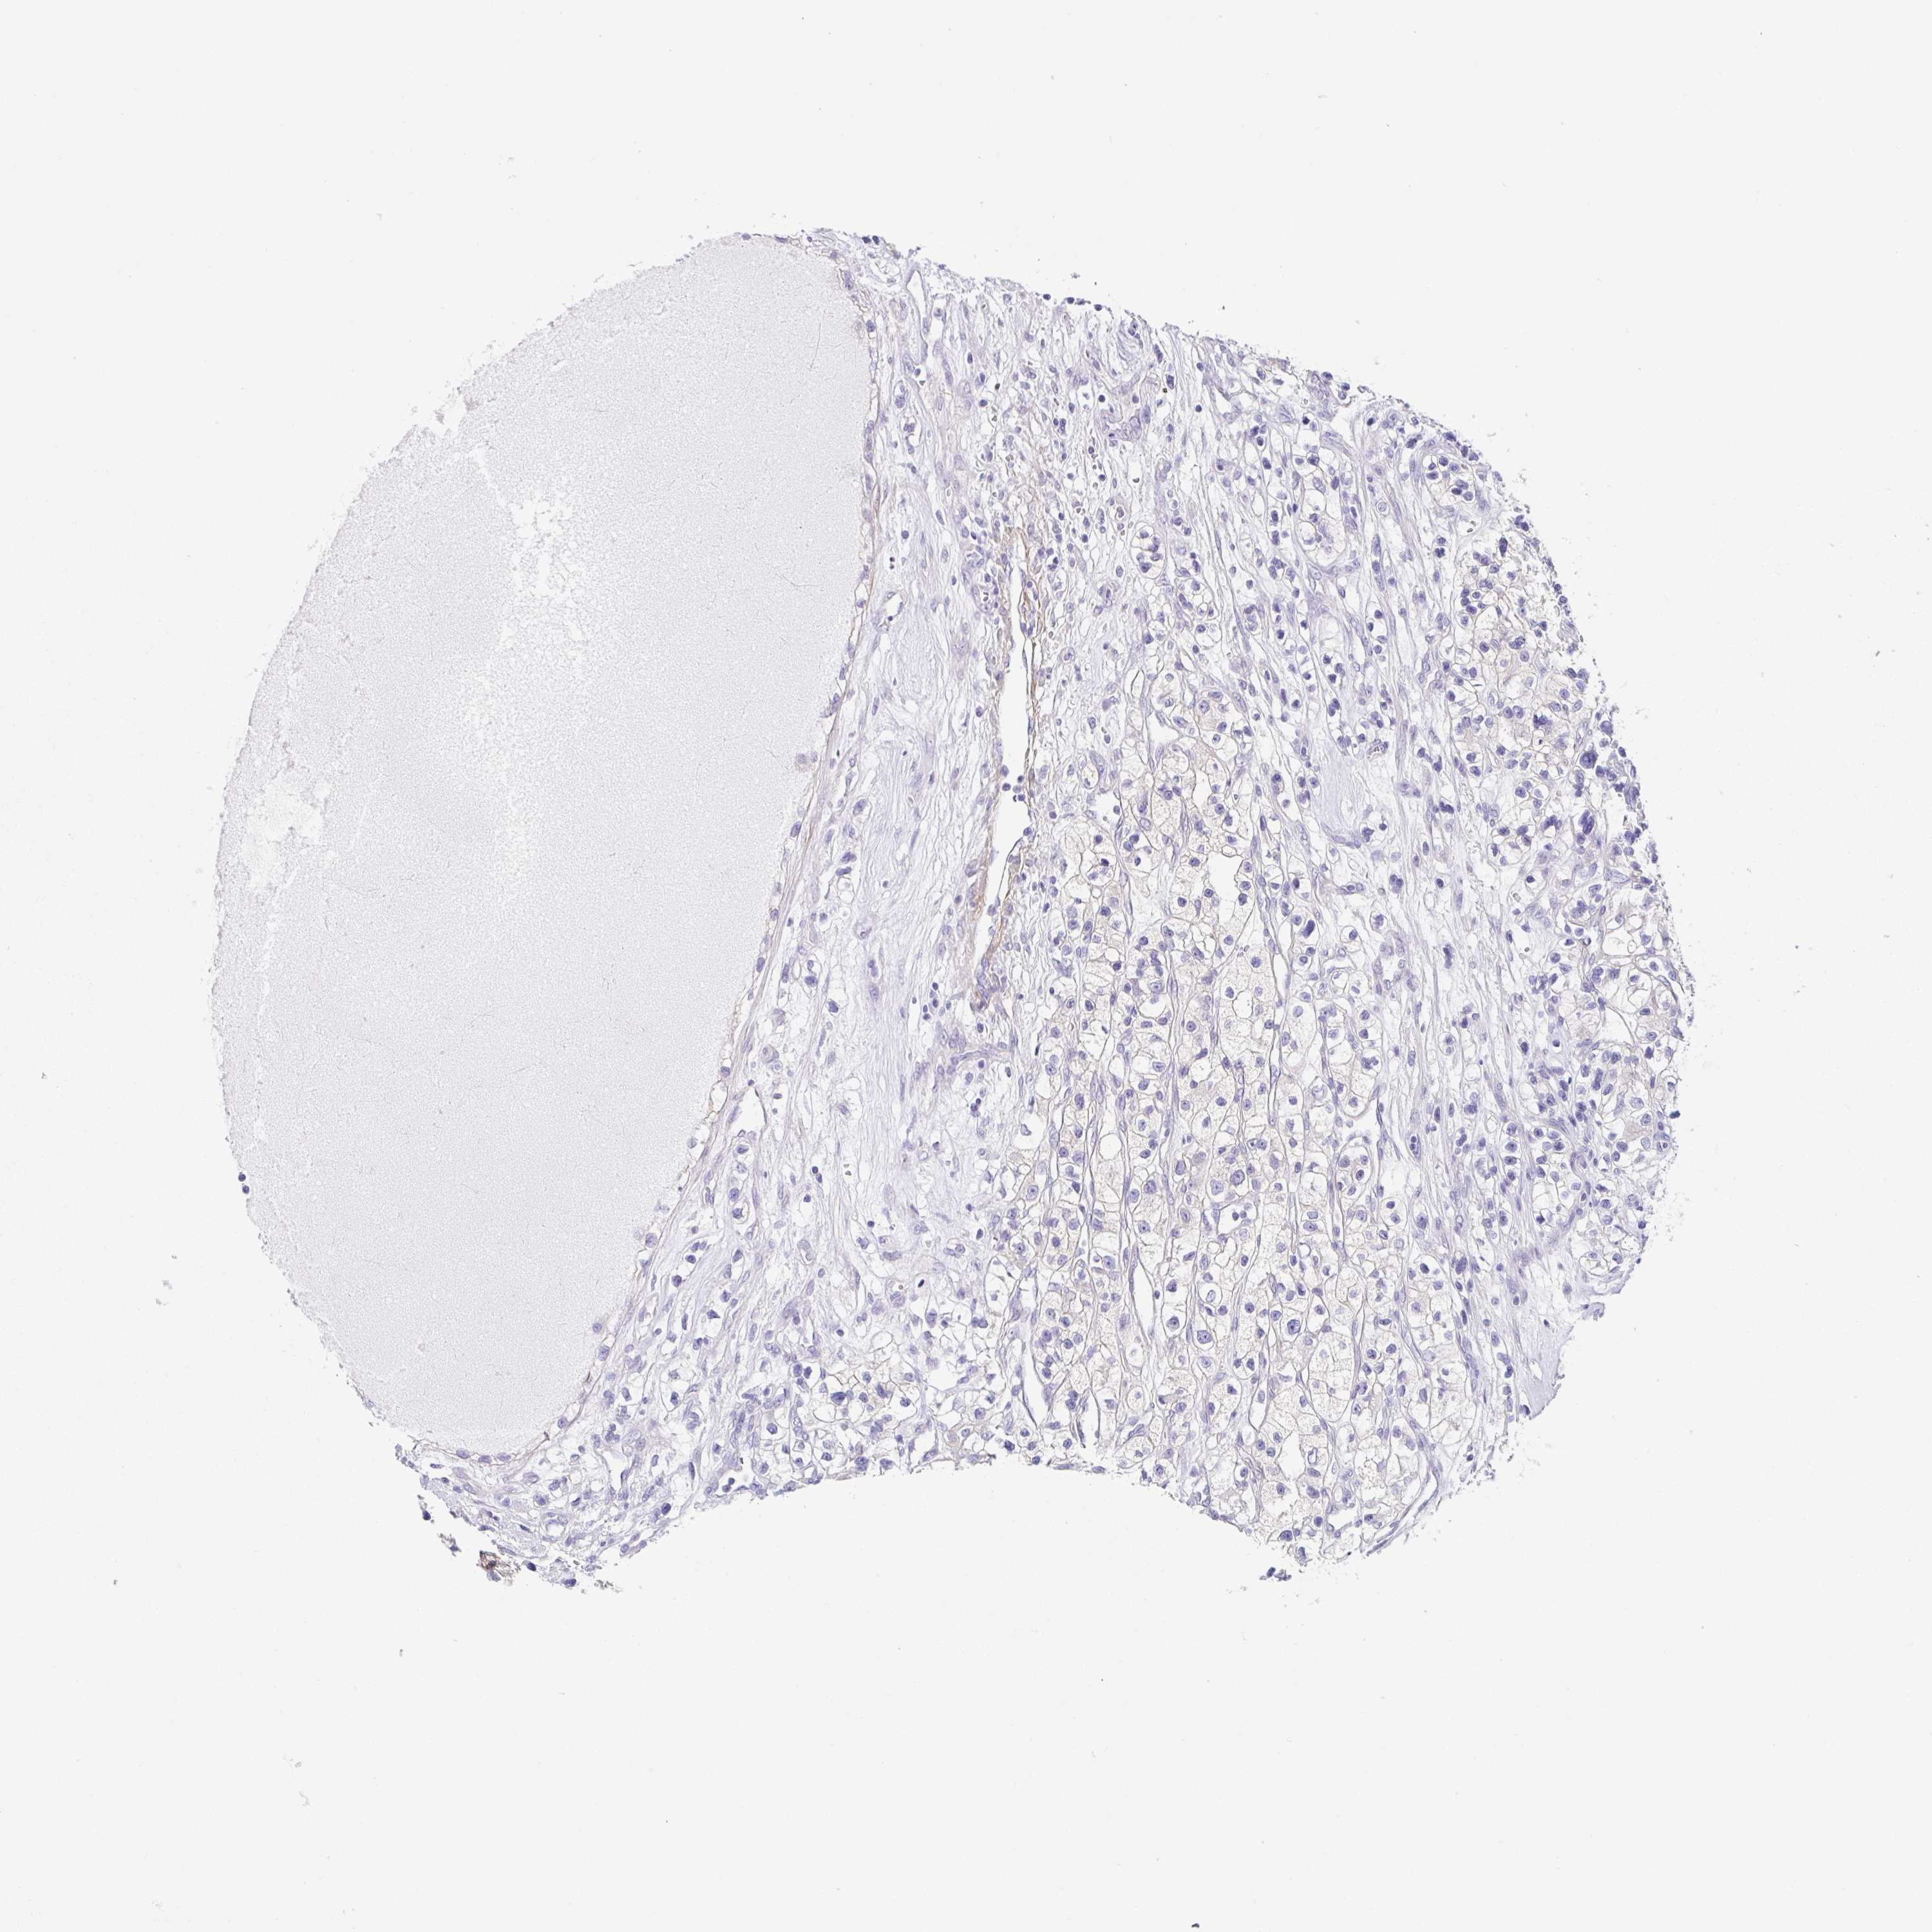

KIDNEY RENAL CLEAR CELL CARCINOMA (VALIDATION) - Interactive survival scatter ploti

The Survival Scatter plot shows the clinical status (i.e. dead or alive) for all individuals in the patient cohort, based on the same data that underlies the corresponding Kaplan-Meier plots. Patients that are alive at last time for follow-up are shown in blue and patients who have died during the study are shown in red.

The x-axis shows the expression levels (FPKM) of the investigated gene in the tumor tissue at the time of diagnosis. The y-axis shows the follow-up time after diagnosis (years). Both axes are complimented with kernel density curves demonstrating the data density over the axes. The top density plot shows the expression levels (FPKM) distribution among dead (red) and alive patients (blue). The right density plot shows the data density of the survived years of dead patients with high and low expression levels respectively, stratified using the cutoff indicated by the vertical dashed line through the Survival Scatter plot. This cutoff is automatically defined based on the FPKM cutoff that minimizes the p-score. The cutoff can be changed by dragging the vertical line or by entering a cutoff value in the square labeled "Current cut-off".

Under the Survival Scatter plot the p-score landscape (black curve; left axis) is shown together with dead median separation (red curve; right axis). Dead median separation is the difference in median mRNA expression between patients who have died with high and low expression, respectively. It is calculated as follows: median FPKM expression of dead patients with high expression - median FPKM expression of dead patients with low expression. This is intended to aid the user in visually exploring custom cutoffs and the associated p-scores and dead median separation.

Individual patient data is displayed and can be filtered by clicking on one or more of the category buttons on the top of the page. Categories describing expression level and patient information include: high, low, alive, dead, female, male and tumor stages. The scale of the x-axis can be toggled between linear and log-scale by clicking on the "x log" button. Mouse-over function shows TCGA ID, patient information and mRNA expression (FPKM) for each patient.

& Survival analysisi

Kaplan-Meier plots summarize results from analysis of correlation between mRNA expression level and patient survival. Patients were divided based on level of expression into one of the two groups "low" (under cut off) or "high" (over cut off). X-axis shows time for survival (years) and y-axis shows the probability of survival, where 1.0 corresponds to 100 percent.

DCAF17 is not prognostic in Kidney Renal Clear Cell Carcinoma (validation)

Best expression cut offi

Based on the FPKM value of each gene, patients were classified into two groups and association between prognosis (survival) and gene expression (FPKM) was examined. The best expression cut-off refers the FPKM value that yields maximal difference with regard to survival between the two groups at the lowest log-rank P-value. Best expression cut-off was selected based on survival analysis .

When clicking on this number, the vertical dashed line indicating cut-off, the interactive survival plot, and the Kaplan-Meier curve will be adjusted to show results based on the best expression cut-off.

: 5.98

P scorei

Log-rank P value for Kaplan-Meier plot showing results from analysis of correlation between mRNA expression level and patient survival.

N/A

TCGA RNA samplesi

RNA-seq data is reported as average FPKM (number Fragments Per Kilobase of exon per Million reads), generated by the The Cancer Genome Atlas (TCGA) .

Normal distribution across the dataset is visualized with box plots, shown as median and 25th and 75th percentiles. Points are displayed as outliers if they are above or below 1.5 times the interquartile range. FPKM values of the individual samples are presented next to the box plot.

Average pTPM 6.5

Number of samples 100